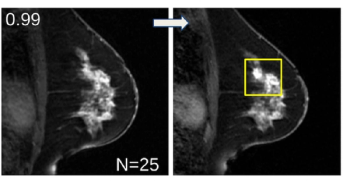

Employing advanced deep learning convolutional neural networks, ProFound Detection Version 4.0 reportedly offers a 50 percent improvement in detecting cancer in dense breasts in comparison to the previous version of the software.

An artificial intelligence (AI) model demonstrated a 72 percent AUC for predicting breast cancer one year before a subsequent MRI.